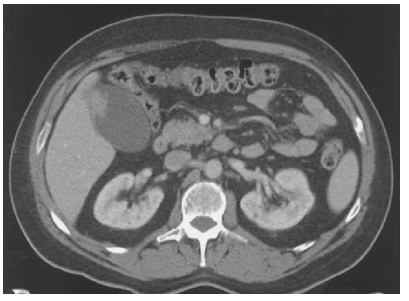

Mulher 57 anos. Assintomática do ponto digestivo. Realizou TC do abdome sem contraste para avaliação de cólica nefrética e suspeita de ureterolitíiase.

Após avaliação da imagem abaixo, você indicaria qual procedimento cirúrgico?

Enunciado 4244948-1